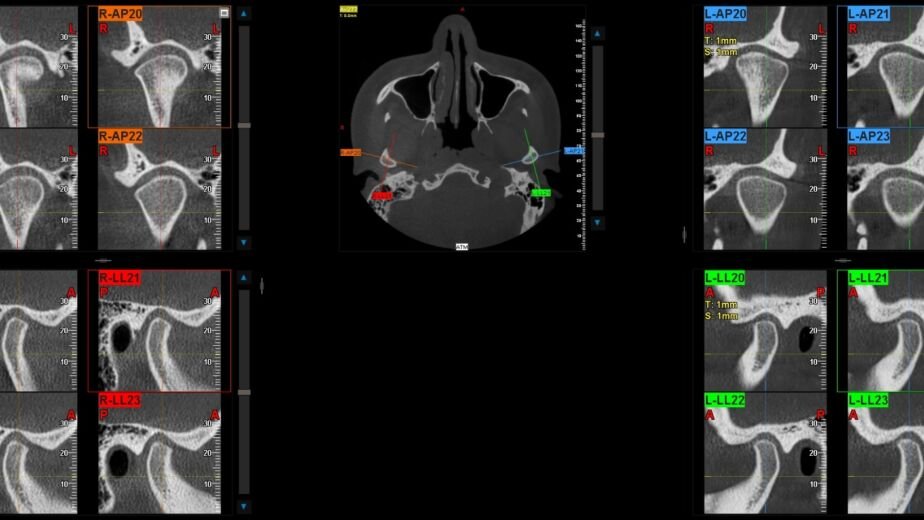

La tecnología detrás del TAC macizofacial utiliza rayos X para crear imágenes en múltiples planos, lo que permite a los odontólogos y cirujanos maxilofaciales visualizar áreas específicas con gran claridad. Esta capacidad de obtener imágenes en 3D es fundamental para un diagnóstico preciso y para la planificación de tratamientos quirúrgicos o restaurativos. En resumen, el TAC macizofacial se ha convertido en una herramienta indispensable en la odontología moderna, mejorando significativamente la calidad del diagnóstico y el tratamiento.

- El examen de tac macizofacial se realiza con un escáner de tomografía computarizada que gira alrededor de la cabeza del paciente para obtener imágenes tridimensionales detalladas de la estructura facial y dental.

Una de las principales ventajas del TAC macizofacial es su capacidad para proporcionar imágenes tridimensionales que permiten una evaluación más completa de la anatomía dental. Esto es especialmente beneficioso en casos donde se requiere una visualización detallada de estructuras complejas, como los senos paranasales o las raíces dentales. La información obtenida a través del TAC puede ser decisiva para establecer un diagnóstico correcto y para elegir el tratamiento más adecuado.

El TAC macizofacial desempeña un papel esencial en la planificación de tratamientos dentales complejos. Por ejemplo, en la colocación de implantes dentales, es crucial conocer la densidad ósea y la ubicación exacta de las estructuras anatómicas cercanas, como nervios y senos maxilares. Con las imágenes obtenidas a través del TAC, los odontólogos pueden diseñar un plan quirúrgico personalizado que minimice riesgos y maximice la eficacia del tratamiento.

La tecnología utilizada en el examen de TAC macizofacial ha avanzado significativamente en las últimas décadas.Los escáneres modernos son capaces de generar imágenes con alta resolución y menor exposición a radiación gracias a técnicas avanzadas como la reconstrucción volumétrica y algoritmos sofisticados que optimizan la calidad de imagen. Estos avances han permitido que los profesionales obtengan información más precisa y detallada sobre la anatomía dental y maxilofacial.

Además, los sistemas informáticos asociados al TAC permiten un análisis más eficiente y efectivo de las imágenes obtenidas. Los odontólogos pueden utilizar software especializado para manipular las imágenes tridimensionales, facilitando así la identificación de problemas específicos y mejorando la planificación del tratamiento. Esta integración entre tecnología avanzada y odontología ha revolucionado la forma en que se diagnostican y tratan las afecciones dentales.